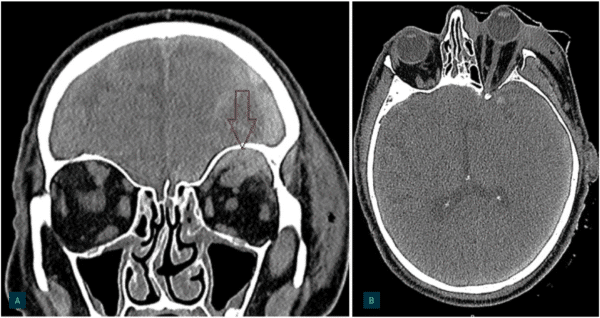

Ved høyt trykk i orbita vil sirkulasjon i intraorbitale arterier og vener avta. Dette kan føre til irreversibel skade på netthinnen eller n. opticus. Nedsatt visus, påvirket fargesyn, smerter, frempressing av øyet (proptose), påvirket pupillerefleks, oftalmoplegi samt kvalme og oppkast kan alle være tegn på økt intraorbitalt trykk (19). Retrobulbære hematomer kan påvises av CT-undersøkelse, som også kan avdekke eventuell proptose og strekk på n. opticus (Bilde 1) (20). Tilstanden krever rask behandling, da irreversibel skade på netthinnen og synsnerven kan skje innen 60-100 minutter (21-24).

BILDE 1: CT ansiktskjelett. A) Venstresidig zygomafraktur (ikke synlig) med tilgrensende retrobulbær blødning (markert med rød pil).

B) I axialplan sees typisk konisk utseende «tenting» av bulbus hos samme pasient. Samtykke til publisering av CT-bilder er innhentet fra pasienten.